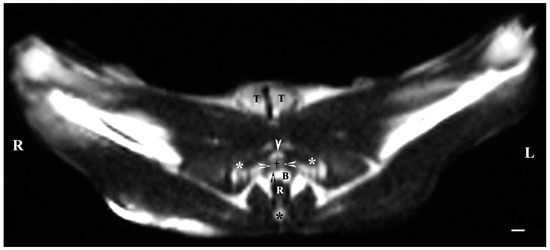

On transverse T2-weighted imaging in the corresponding planes (first caudal vertebra, then the plane between the first and second caudal vertebrae—dorsal; the caudal part of the pelvic symphysis—ventral; the plate of ischium—lateral), the rabbit bulbourethral glands were identified. They appeared as soft-tissue, homogeneous organs with hyper-intense characteristics compared to the peripheral soft tissue landmarks (urethra, rectum, pelvic diaphragm), except for the penile bulb and the beginning of the penile root. The latter were visualized as findings with the highest intensity relative to structures in the perineum. The shape of the glands was oval. The glandular capsule was differentiated as a hypo-intense peripheral ring-like finding. The ventrally located pelvic part of the urethra was hypo-intense and imaged dorsally to the caudal part of the pelvic symphysis. The rectum showed a hypo-intense image that was localized dorsally to the penile bulb and root and ventrally to the first caudal vertebra (Figure 1).

Figure 1. T2-weighted transverse image of rabbit pelvis in the plane through the level of the first caudal vertebra (white star): R—right; L—left. Bulbourethral glands (white horizontal arrows), the pelvic part of the urethra (white cross), penile bulb (B), rectum (R), ischial bones (black stars), the caudal part of the pelvic symphysis (white perpendicular arrow), pelvic diaphragm (black inclined arrows), and testes (T). Line—10 mm.